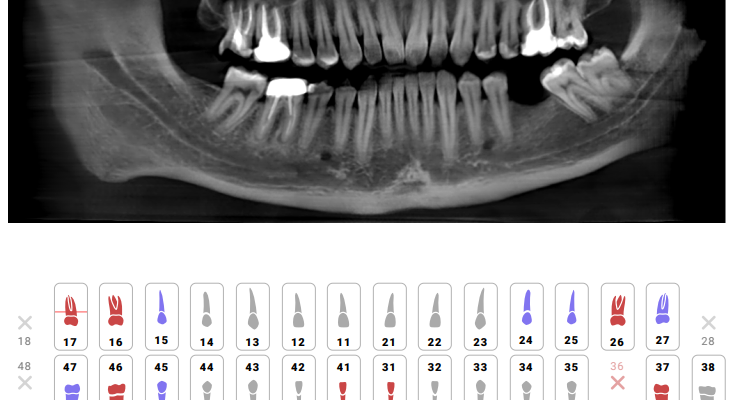

ИИ в стоматологии: Революция у вас во рту! Приветствуем вас‚ дорогие читатели! Сегодня мы погрузимся в захватывающий мир стоматологии будущего‚

ИИ в Стоматологии: Как алгоритмы предсказывают рецессию десны и спасают улыбки В мире, где технологии проникают во все сферы нашей жизни, стоматология

Искусственный Интеллект в Стоматологии: Как Прогнозировать Подвижность Зубов и Сохранить Улыбку Привет, друзья! Сегодня мы погрузимся в захватывающий мир

ИИ в стоматологии: Прогнозируем улыбку будущего! Приветствуем вас, дорогие читатели, на страницах нашего блога! Сегодня мы погрузимся в захватывающий мир

Искусственный Интеллект в Стоматологии: Прогнозируем Будущее Здоровой Улыбки В мире, где технологии развиваются с невероятной скоростью, искусственный